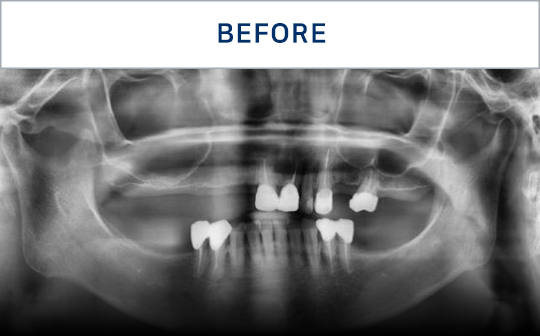

种植牙是在精准诊断与治疗计划的基础上,

通过多个步骤进行的治疗方式

会根据患者的口腔状况, 分阶段安全推进

通过CT, 扫描等数字设

备拍摄后,

进行精密分析

考虑骨骼状态与神经位置,

制定种植位置与手术计划